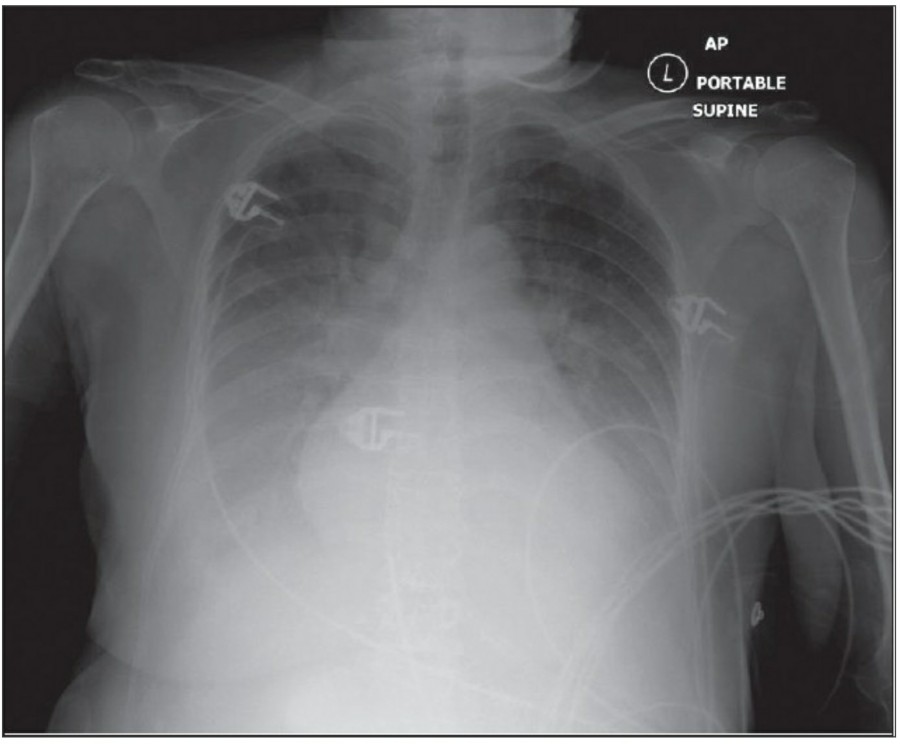

Pleural effusion

방사선 소견상 Pleural effusion은 환자 흉부의 dependent area에 고인다. Erect position에서 확인하기가 쉬운데, 폐의 base에 고임으로써 costophrenic angle blunting을 보이고 lower lobe vessel들의 흐리게 한다. Supine position에서는 확인이 더 어려운데, pleural fluid는 posterior basilar space에 고여서 폐 base 쪽으로 intensity가 증가하는 homogenous density를 보인다. 정상적인 bronchoalveolar marking은 이와 같은 veil-like density 안에서 확인 가능하다. Fluid 양이 늘어나면서 diaphragm의 윤곽이 흐릿해지고 costophrenic angle도 없어지는데, 이 costophrenic angle blunting이 없더라도 pleural space에 1L 정도의 pleural fluid가 있을 수 있다는 것을 기억해야 한다. 그 양이 더욱 늘어날 수록 fluid는 lung의 apex에서 pleural cap으로 나타날 수 있으며, 이는 supine position에서도 확인 가능하다. Pleural fluid는 lung의 medial side에 고일 수도 있으며 이는 mediastinum의 확장으로 보일 수도 있다.

적은 양의 pleural fluid는 꼼꼼히 확인하더라도 supine radiograph에서 놓칠 수 있는데, 만약 chest X ray에서 보이지 않지만 임상적으로 의심이 되는 경우에는 lateral decubitus film으로 확인해 볼 수 있다. Fluid는 dependent position에 고이므로 환자를 의심되는 방향으로 옆으로 눕혀야 한다. Lateral decubitus film은 적은 양의 pleural fluiid는 물론이고 loculated effusion과 free effusion을 확진하는 데도 도움이 된다. 특히 loculated effusion은 한 개 이상의 drain이 필요할 수 있으므로 pleural drainage를 고려할 때 특히 중요한 검사이다. 중환자에서 흔하게 나타나는 subplumonic effusion은 lung base에 존재하는 pleural effusion을 말하는데, chest X ray 상에서 raised hemidiaphragm with flattening and lateral displacement of the dome 형태로 나타나며, lateral decubitus film이 도움이 된다.

Loculated pleural effusion의 진단은 쉽지 않은데, 특히 fissure 안에 있을 때 어렵다. Loculted effusion이 minor fissure 안에 있고 right middle lobe atelectasis가 있다면 supine chest radiograph에서 감별이 어려운데, interlobular effusion은 biconvex edges와 homogenous density로 나타나고 minor fissure는 유지되는 반면, atelectasis는 concave margin과 inhomogenous density로 나타나며 right heart border와 minor fissure가 보이지 않게 된다. 이런 경우 erect lateral radiograph나 CT가 도움이 될 수 있다.